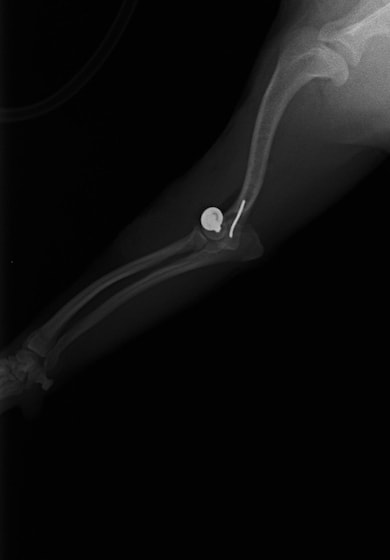

症例3:キルシュナーワイヤーのピンニングによる整復

ペルシャ猫 11ヶ月齢 雄

他院にて左大腿骨遠位の成長板骨折(salter-harrisⅠ型)が認められており、治療相談を目的として来院。当院にて、キルシュナーワイヤーを用いたピンニングにより骨折部位の整復を行いました。術後の経過は良好で、現在も経過観察中です。

術前レントゲン

術後レントゲン

Arthrex社のターゲティングデバイスを用いてピンニングの位置を調整することで、確実な固定を行っています。当院ではこの手術器具以外にも、人の手術にも使用される様々な器具を導入し、手術精度を高め、また医療メーカーと新しい器具の開発、試作にも取り組んでおります。